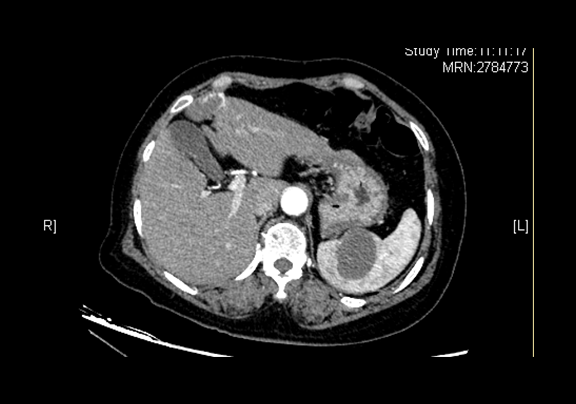

术前CT检查:

平衡期

全腹CT 肝左叶内略低密度灶,脾脏内略低密度灶

将0.625mm双源薄层CT资料的静脉期和动脉期Dicom格式文件导入海信CAS系统。

通过调节窗宽窗位调整CT序号,对肿瘤,肝实质,胆囊,下腔静脉,肿瘤,肝动脉、门静脉及肝静脉等进行三维重建;系统自动计算肿瘤体积和肝脏体积。